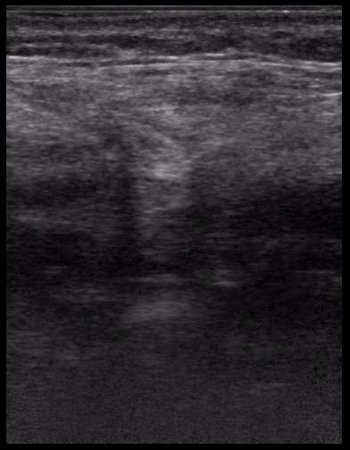

эхинококк лёгкого

2.JPG

32.JPG